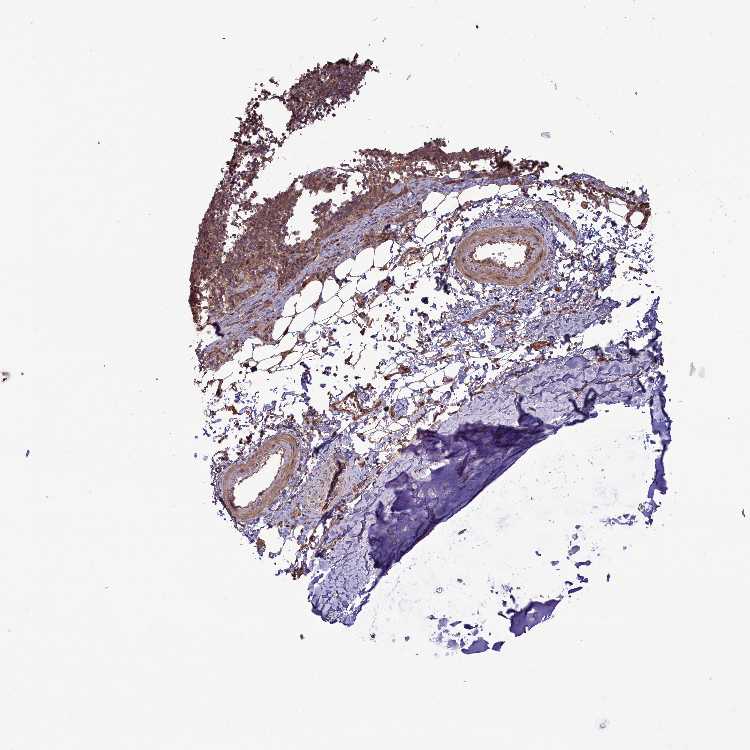

SOFT TISSUE 2 - Antibody stainingi

Antibody staining in the annotated cell types in the current human tissue is reported as not detected, low, medium, or high, based on conventional immunohistochemistry profiling in selected tissues. This score is based on the combination of the staining intensity and fraction of stained cells.

Each image is clickable and will lead to virtual microscopy that enables deeper exploration of all samples and also displays staining intensity scores, fraction scores and subcellular localization as well as patient and tissue information for each sample.

Antibody HPA041501Antibody HPA041736

Chondrocytes LowMedium

Fibroblasts MediumMedium

Peripheral nerve -High